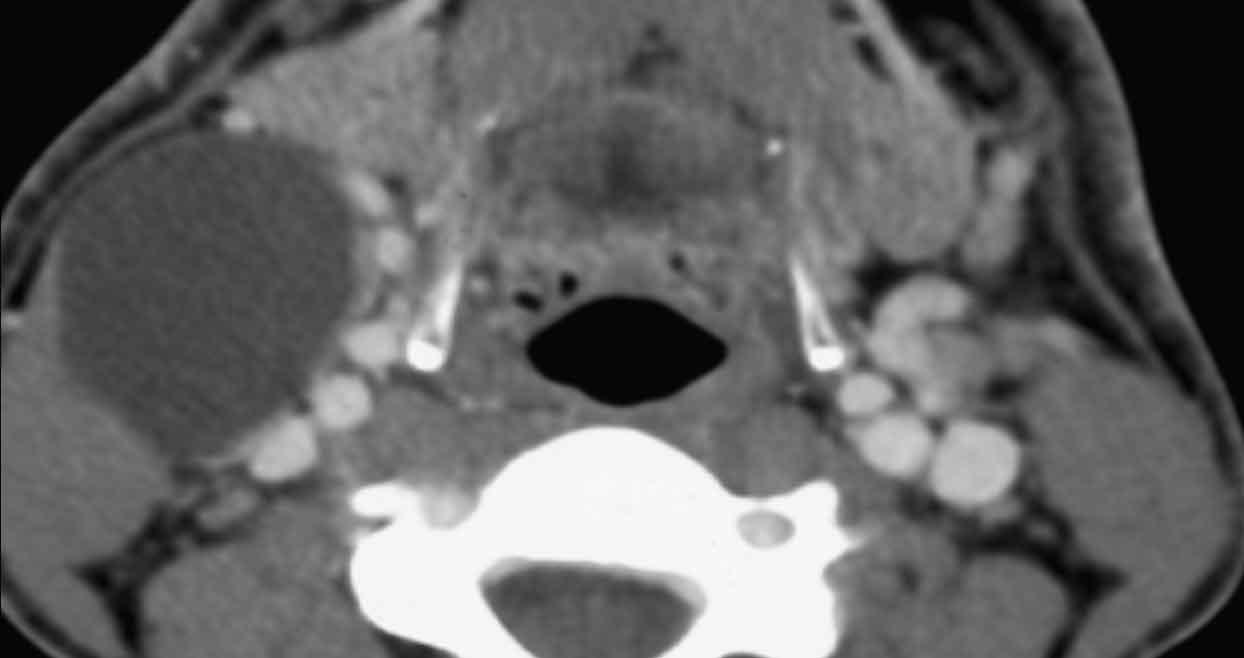

Bệnh nhân nữ 62 tuổi.

CT xoang được chỉ định bởi bác sĩ tai mũi họng. Thông tin lâm sàng: ‘viêm xoang một bên mạn tính’.

Hình ảnh

Có hình ảnh mờ đặc do mô mềm tại xoang hàm, xoang sàng và xoang trán bên phải (gọi là ‘kiểu tắc nghẽn phễu’).

Như đã đề cập, đây là một dấu hiệu cảnh báo.

Hãy quan sát các hình ảnh tiếp theo và cố gắng xác định liệu có tổn thương ác tính nào gây ra kiểu tắc nghẽn phễu này không (hay có nguyên nhân nào khác không?)

Có hình ảnh thấu quang quanh chóp răng tại vùng chân răng hàm lớn trên bên phải, gợi ý nhiễm trùng răng (đầu mũi tên đen).

So sánh với bên trái bình thường trên ảnh cắt ngang (đầu mũi tên trắng).

Thăm khám lâm sàng bổ sung đã loại trừ tổn thương ác tính.

Bệnh nhân được chuyển khám răng hàm mặt vì nhiễm trùng răng hoàn toàn có thể là nguyên nhân gây viêm xoang mạn tính một bên.

Lưu ý: Vì lý do này, việc bao gồm vùng xương hàm trên trong trường chụp của CT xoang là điều hết sức quan trọng.